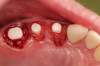

Fig 2. Extractions and immediate placement.

Figure 2

Figure 1 and Figure 2 depict the preoperative image and subsequent removal of three posterior teeth, immediate placement of zirconia-oxide ceramic dental implants, and soft-tissue augmentation with platelet-rich fibrin (PRF) to enhance the soft-tissue architecture surrounding the ceramic implants. The teeth were removed atraumatically and without suture placement. Because the implants were one-piece in stature (the abutment was incorporated into the implant), the recommendation was to splint the multiple units to minimize the lateral forces from mastication, swallowing, and tongue movement.